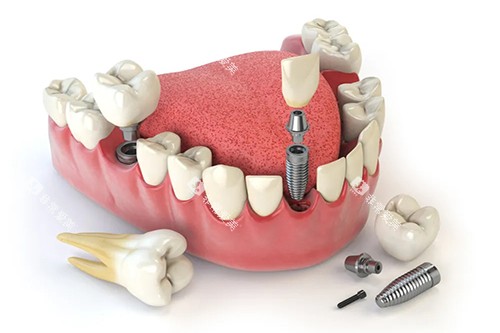

如智能化口腔全景机,能够快速、比较准地获取口腔超全影像,为医生的诊断提供清晰、详细的依据;靠前的种植牙系统,确保种植牙手术的更准一些性和可靠性;舒适的牙科综合治疗椅,让患者在治疗过程中感受到更多的舒适和便利。

在种植牙领域,医院的医生凭借过关的技术和丰富的经验,成功为众多缺牙患者种上了新牙,修养了患者的咀嚼功能和美观。